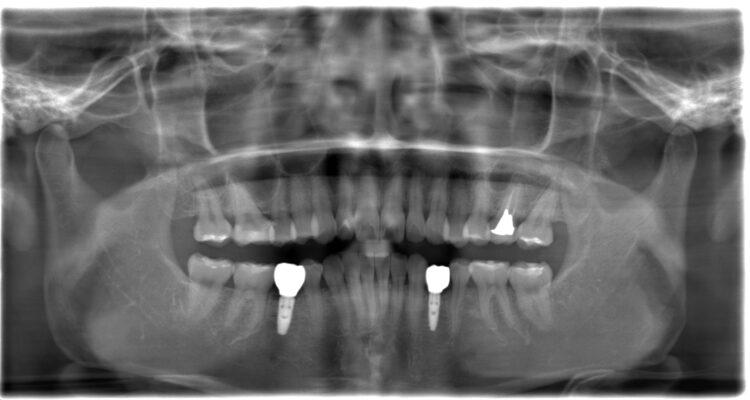

インプラント手術後

インプラント手術し両側にインプラントを埋入しています。